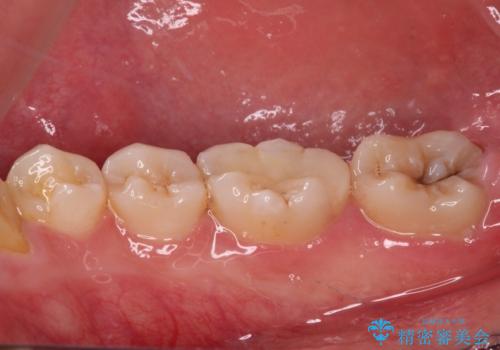

- 矯正治療後に目立つ銀歯を白くしたいとのことで来院された患者様です。

右下の銀の詰め物は、外してむし歯を除去した後、セラミックインレーにて修復することとしました。

適合の良いセラミック治療は、むし歯再発のリスクが低いです。

目立つ銀歯がなくなり、患者様は大変満足されました。